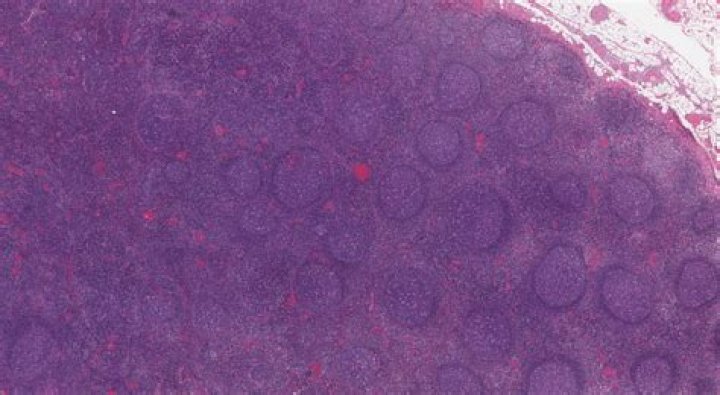

Is reactive lymphoid hyperplasia cancer?

Reactive lymphoid hyperplasia (RLH) is a rare and benign lesion found in organs of the gastrointestinal tract, skin, lung, orbit, and more rarely in the liver. Due to its similar appearance on imaging, it is hard to differentiate from primary liver malignancies.

Reactive lymphoid hyperplasia is a benign nodular lesion characterized by marked proliferation of non-neoplastic, polyclonal lymphocytes forming follicles. The lesion is found in various organs such as skin, orbit, lung, gastrointestinal tract, and liver.

Reactive lymphoid hyperplasia (RLH) has been described as the benign and reversible enlargement of lymphoid tissue secondary to antigen stimulus. There are four patterns which can be seen in RLH: Follicular Pattern, Diffuse Paracortical Hyperplasia, Sinus Histiocytosis and Mixed Pattern.

Background: Reactive lymphoid follicular hyperplasia is a benign proliferation of lymphoid follicles, which can develop wherever lymphoid tissue is present. We present the unique case of an RLFH that involved the radial nerve and presented as a peripheral nerve tumor.